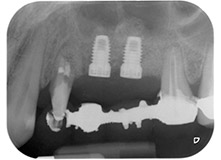

Finally, after periosteal incision, the site was passively sutured with a coronally advanced flap, using 5-0 absorbable suture material (Fig. 15). The postoperative radiograph showed both implants in their correct vertical position (Fig. 16).

Figures 17 and 18 show the clinical result two months after the surgery. Tooth 24 exhibited reduced mobility of Miller class 1, and the soft tissues were free of inflammation. Probing was avoided at this point of time to prevent reinfection and to avoid violating the epithelial attachment. A control visit was scheduled for reentry and placement of healing abutments, six months after the insertion of the implants.